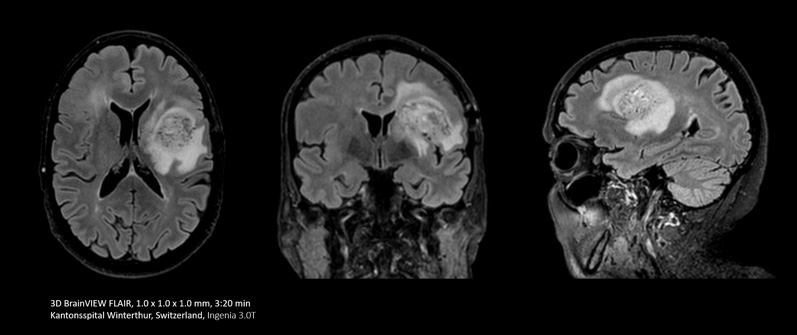

脳や脊椎を検査する場合、Compressed SENSEの能力を活かして2Dシーケンスをより有用な情報が得られる3Dシーケンスに入れ替えることが有効です。これにより、詳細な解剖学的情報が求められる場合でも高い空間分解能が得られます。

Compressed SENSEを使用すると、単一方向の2D FLAIRを多断面観察が可能な3D FLAIRに入れ替えることができます。この3D FLAIRの撮像時間は3分30秒です。

これまで多くの脳の画像診断を行ってきましたが、以前はFLAIRシーケンスを5 mm厚のスライスで使用していました。現在では、Compressed SENSEを使用して、以前は約6分間かかっていた3D FLAIRを3分30秒で完了できるようになりました」

Mark Oswood医師、医学博士、神経放射線科医、Hennepin Healthcare、ミネアポリス、米国